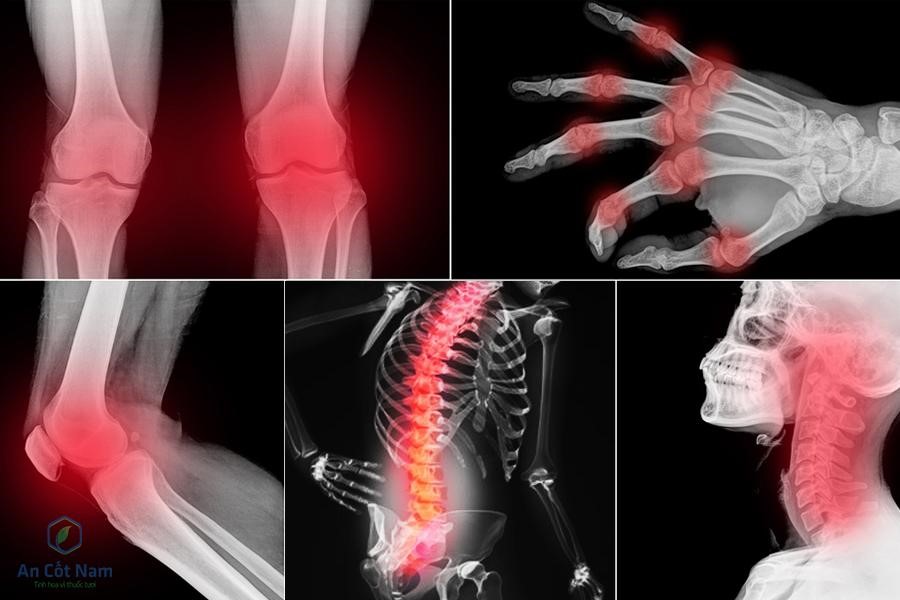

Triệu chứng của bệnh thoái hóa khớp

Những bệnh nhân bị thoái hóa khớp sẽ chịu những cơn đau nhức quanh khớp dai dẳng. Nếu hoạt động bình thường thì chỉ đau âm ỉ thôi nhưng nếu vận động mạnh, bị chấn động hoặc những lúc “trái gió trở trời” thì cơn đau khớp cấp tính và dữ dội hơn. Khi bị đau khớp, chỉ cần nghỉ ngơi hợp lý thì cơn đau nhanh chóng tan mất.

Cứng khớp là triệu chứng hàng đầu của bệnh thoái hóa khớp. Thông thường, hiện tượng cứng khớp sẽ xảy ra vào buổi sáng sau khi ngủ dậy. Khi bị cứng khớp, người bệnh sẽ khó khăn trong việc thực hiện các cử động, ảnh hưởng nghiêm trọng đến việc đi lại và các hoạt động sống. Khi bị cứng khớp, chỉ cần nghỉ ngơi tầm 10 – 30 phút thì cơn đau sẽ giảm dần. Tùy vào tình trạng bệnh thoái hóa khớp mà cơn đau cứng khớp nặng nhẹ khác nhau, nếu bị thoái hóa khớp nặng thì triệu chứng cứng khớp sẽ kéo dài hơn và đau nhiều hơn.

Nghe thấy tiếng kêu lạo xạo khi cử động mạnh là triệu chứng dễ nhận biết nhất của bệnh thoái hóa khớp. Giải thích cho hiện tượng này, các chuyên gia cho rằng, khi bị thoái hóa khớp thì phần sụn và đệm giữa hai đầu xương bị hao mòn, khi di chuyển sẽ khiến cho hai đầu xương cọ sát vào và va chạm vào phần sụn bị bào mòn gây tiếng lạo xạo. Kèm theo những tiếng kêu lạo xạo đó là những cơn đau nhức dữ dội.

Teo cơ, khớp sưng đau hoặc biến dạng là triệu chứng hay gặp của bệnh thoái hóa khớp. Có thể là phần đầu gối bị di lệch khỏi trục, các ngón tay bị u cục và gồ ghề, ngón chân thì cong vẹo,… gây khó khăn trong mọi hoạt động sống, ảnh hưởng nghiêm trọng đến chất lượng cuộc sống.

Cách loại thoái hóa khớp thường gặp là thoái hóa khớp gối, thoái hóa khớp vai, thoái hóa khớp háng, thoái hóa khớp tay, thoái hóa khớp chân...